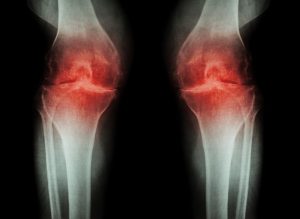

LESIONES FRECUENTES

DE LA RODILLA